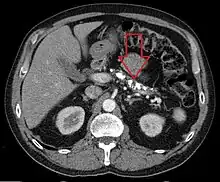

Axial CT showing multiple calcifications in the pancreas in a patient with chronic pancreatitis

Computed tomography, magnetic resonance cholangiopancreatography (MRCP), and endoscopic ultrasound (EUS) all have similar sensitivity and specificity for diagnosing chronic pancreatitis.[4] MRCP is particularly utilized for its sensitivity in imaging the pancreatic ducts and bile ducts for associated changes such as stones or strictures.[4][12] A biopsy of the pancreas is not required for the diagnosis.[4] On imaging, pancreatic and bile duct dilatation, atrophy of the pancreas, multiple calcifications of the pancreas, and enlargement of pancreatic glands can be found.[12]